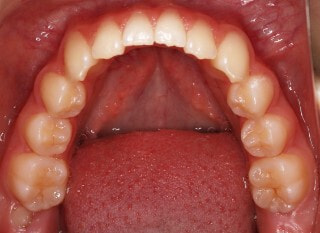

小児期第二段階

開始時